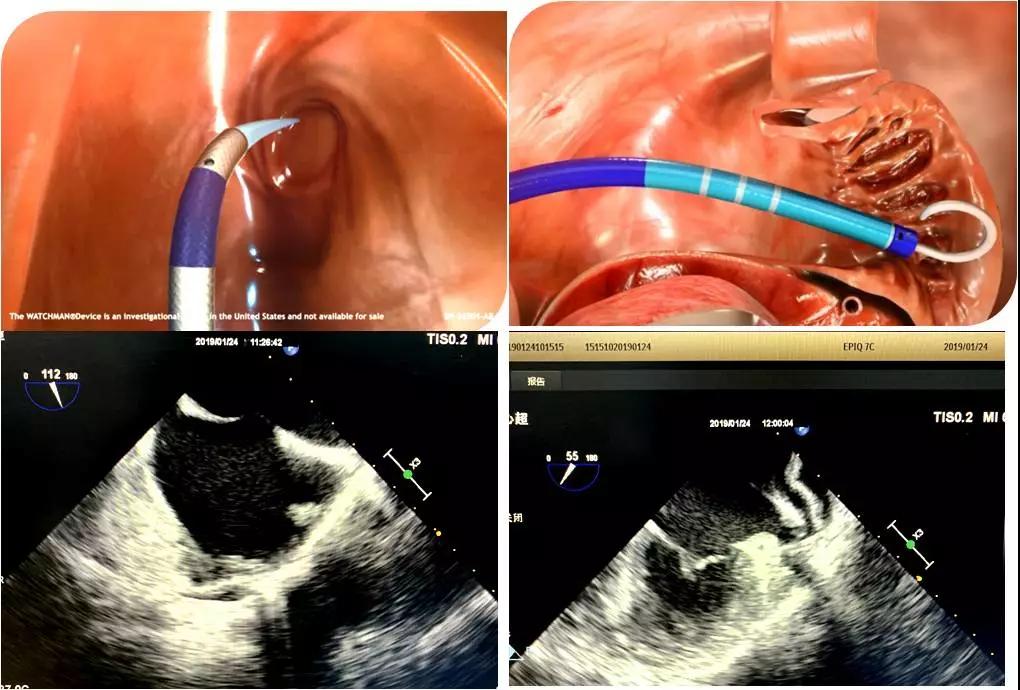

经食管超声心动图是将专业的食道超声探头从食道进入心脏后方的左心房附近,从心脏后方观察心脏内部病变,避免了肺气的干扰,图像质量明显高于经胸超声,被誉为探查心脏异常“火眼金睛”。

房颤最主要的并发症是血栓栓塞,其中90%以上血栓来源于左心耳。左心耳封堵为心房颤动患者预防脑栓死提供技术支持,逐渐成为有华法林禁忌或不能长期口服华法林患者抗凝治疗的常规选择,很多房颤患者还伴发风湿性心脏病、先天性心脏病及缺血性心肌病、瓣膜病等问题,情况往往综合而复杂。为了准确评估左心耳构造以选择合适的封堵器和植入位置,并对术中穿刺关键步骤及植入准确性实时监测,经食道超声心动图(TEE)越来越多的应用于心脏介入手术的术前及术中评估。

于2019年1月24日上午,心内科主任马锋、副主任医师潘军强在介入室对一例房颤患者进行左心耳封堵术,超声科郑瑜主任为该患者实施了术中经食管超声心动图监测,清晰显示了房间隔的穿刺,并多平面多角度测量左心耳的超声径线,监测鞘管进入左心耳根部,展开与释放封堵器,并及时评估了封堵器的最终位置、稳定性等,经食道超声的“慧眼“监测为该心脏手术的顺利进行提供了有力保障。